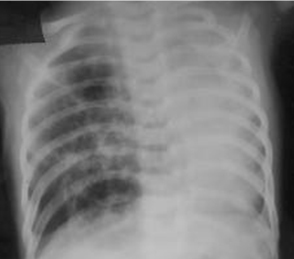

Malformação congênita da via aérea pulmonar (CPAM; antes conhecida como malformação adenomatoide cística congênita [MACC])

Do acervo de Ponthenkandath Sasidharan, MD; usado com permissão